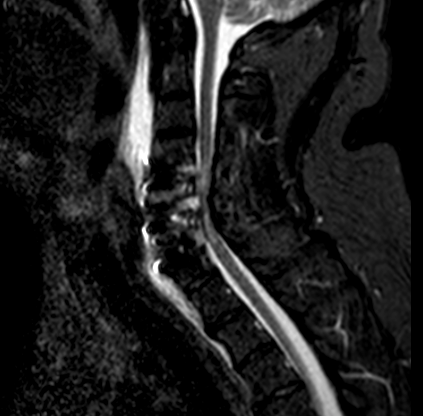

El resultado de la RM cervical planteaba dudas si era necesario o mandatorio realizar una descompresión posterior complementaria. Sin embargo, los parámetros clínicos no sugerían una compresión medular: la evolución lenta a la mejoría de su paresia, la ausencia de progresión de su mielopatía y la ausencia de dolor resultaron determinantes para que se adoptara una actitud conservadora. El paciente fue dado de alta (en plena pandemia de covid) y la evolución fue buena a pesar de que no pudo completar la rehabilitación. Se realizó nueva RM y RX cervical a los seis meses que resultó mucho más concluyente.

A los seis meses de evolución, el paciente sigue pendiente de rehabilitación, ha mejorado su inestabilidad postural y en la marcha aunque persiste la paresia C7 (agravada respecto a preoperatorio, con EMG y registros MNIO con radiculopatía crónica severa).

RM 6 meses

afecta de manera significativa el diámetro del canal vertebral y a la que se realizará seguimiento evolutivo.